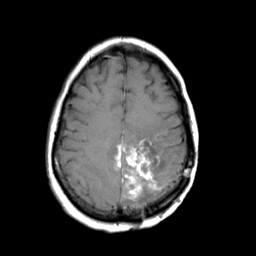

MR Study #3 -- Slice #38

[Home][Help][Clinical][Tour 1][Tour 2][Tour 3] Slice 38